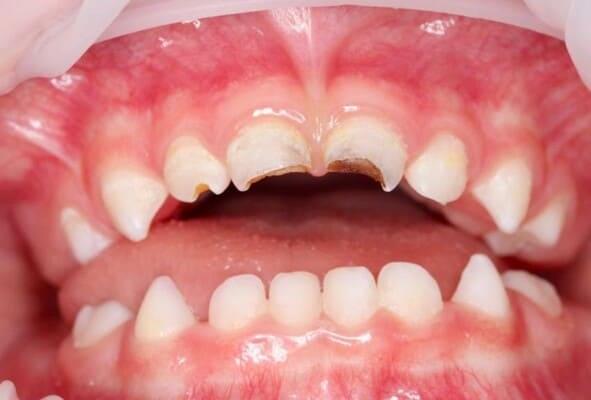

Дівчинка 2 років, але зуби вже мають глибокі ураження із залученням у запальний процес пульпи (“нерва”) зуба. На жаль, так трапляється і зволікати в такому випадку не можна. Було проведено лікування в умовах анестезіологічного забезпечення під контролем досвідченої анестезіологічної команди. Передні зубчики відновлено естетичними коронками, на жувальних зубчиках проведена герметизація фісур, а один вже має глибоке ураження карієсом, тому теж покритий коронкою. Одразу після лікування ясна можуть виглядати дещо травмованими, але за кілька днів вони повністю відновляться.